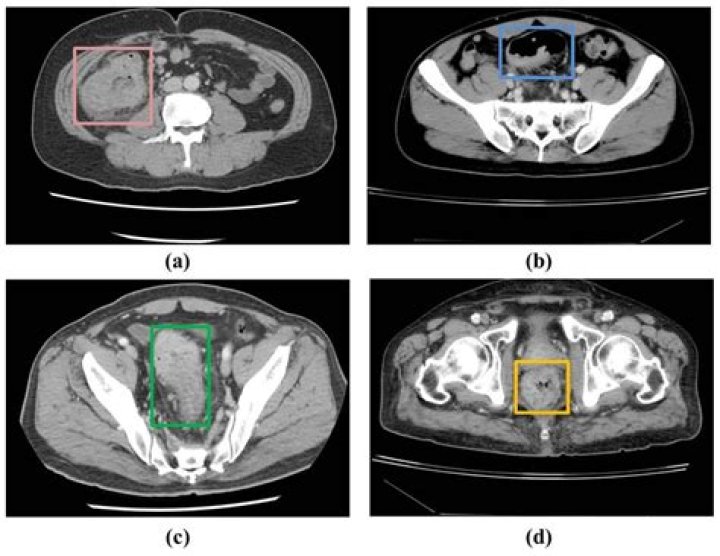

CT scans can help diagnose a peptic ulcer that has created a hole in the wall of your stomach or small intestine.

Conclusions: Although CT has low sensitivity for peptic ulcer disease, the miss rate for visible peptic ulcers is high. Increased awareness, multiplanar imaging review, and identification of ancillary findings may improve sensitivity for gastroduodenal ulcers.

What can a CT scan show in the stomach?

An abdominal CAT scan can detect signs of inflammation, infection, injury or disease of the liver, spleen, kidneys, bladder, stomach, intestines, pancreas, and adrenal glands. It is also used to look at blood vessels and lymph nodes in the abdomen.